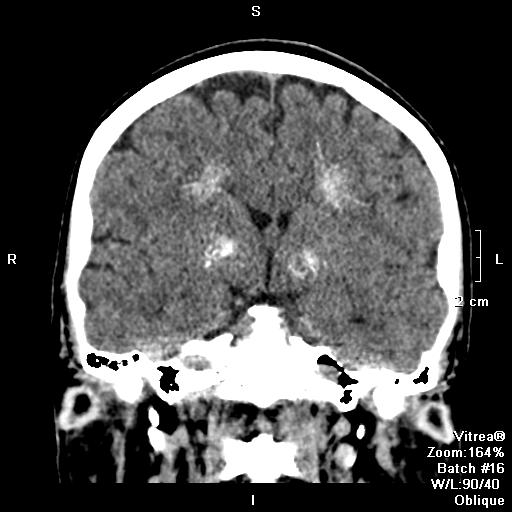

Базальный кальцинат

Базальный кальцинат 109 фотографий